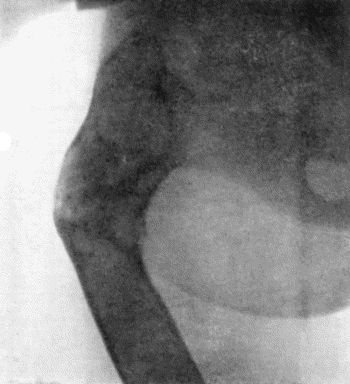

121.Radiogram of Brodie's Abscess in Lower End of Tibia 451